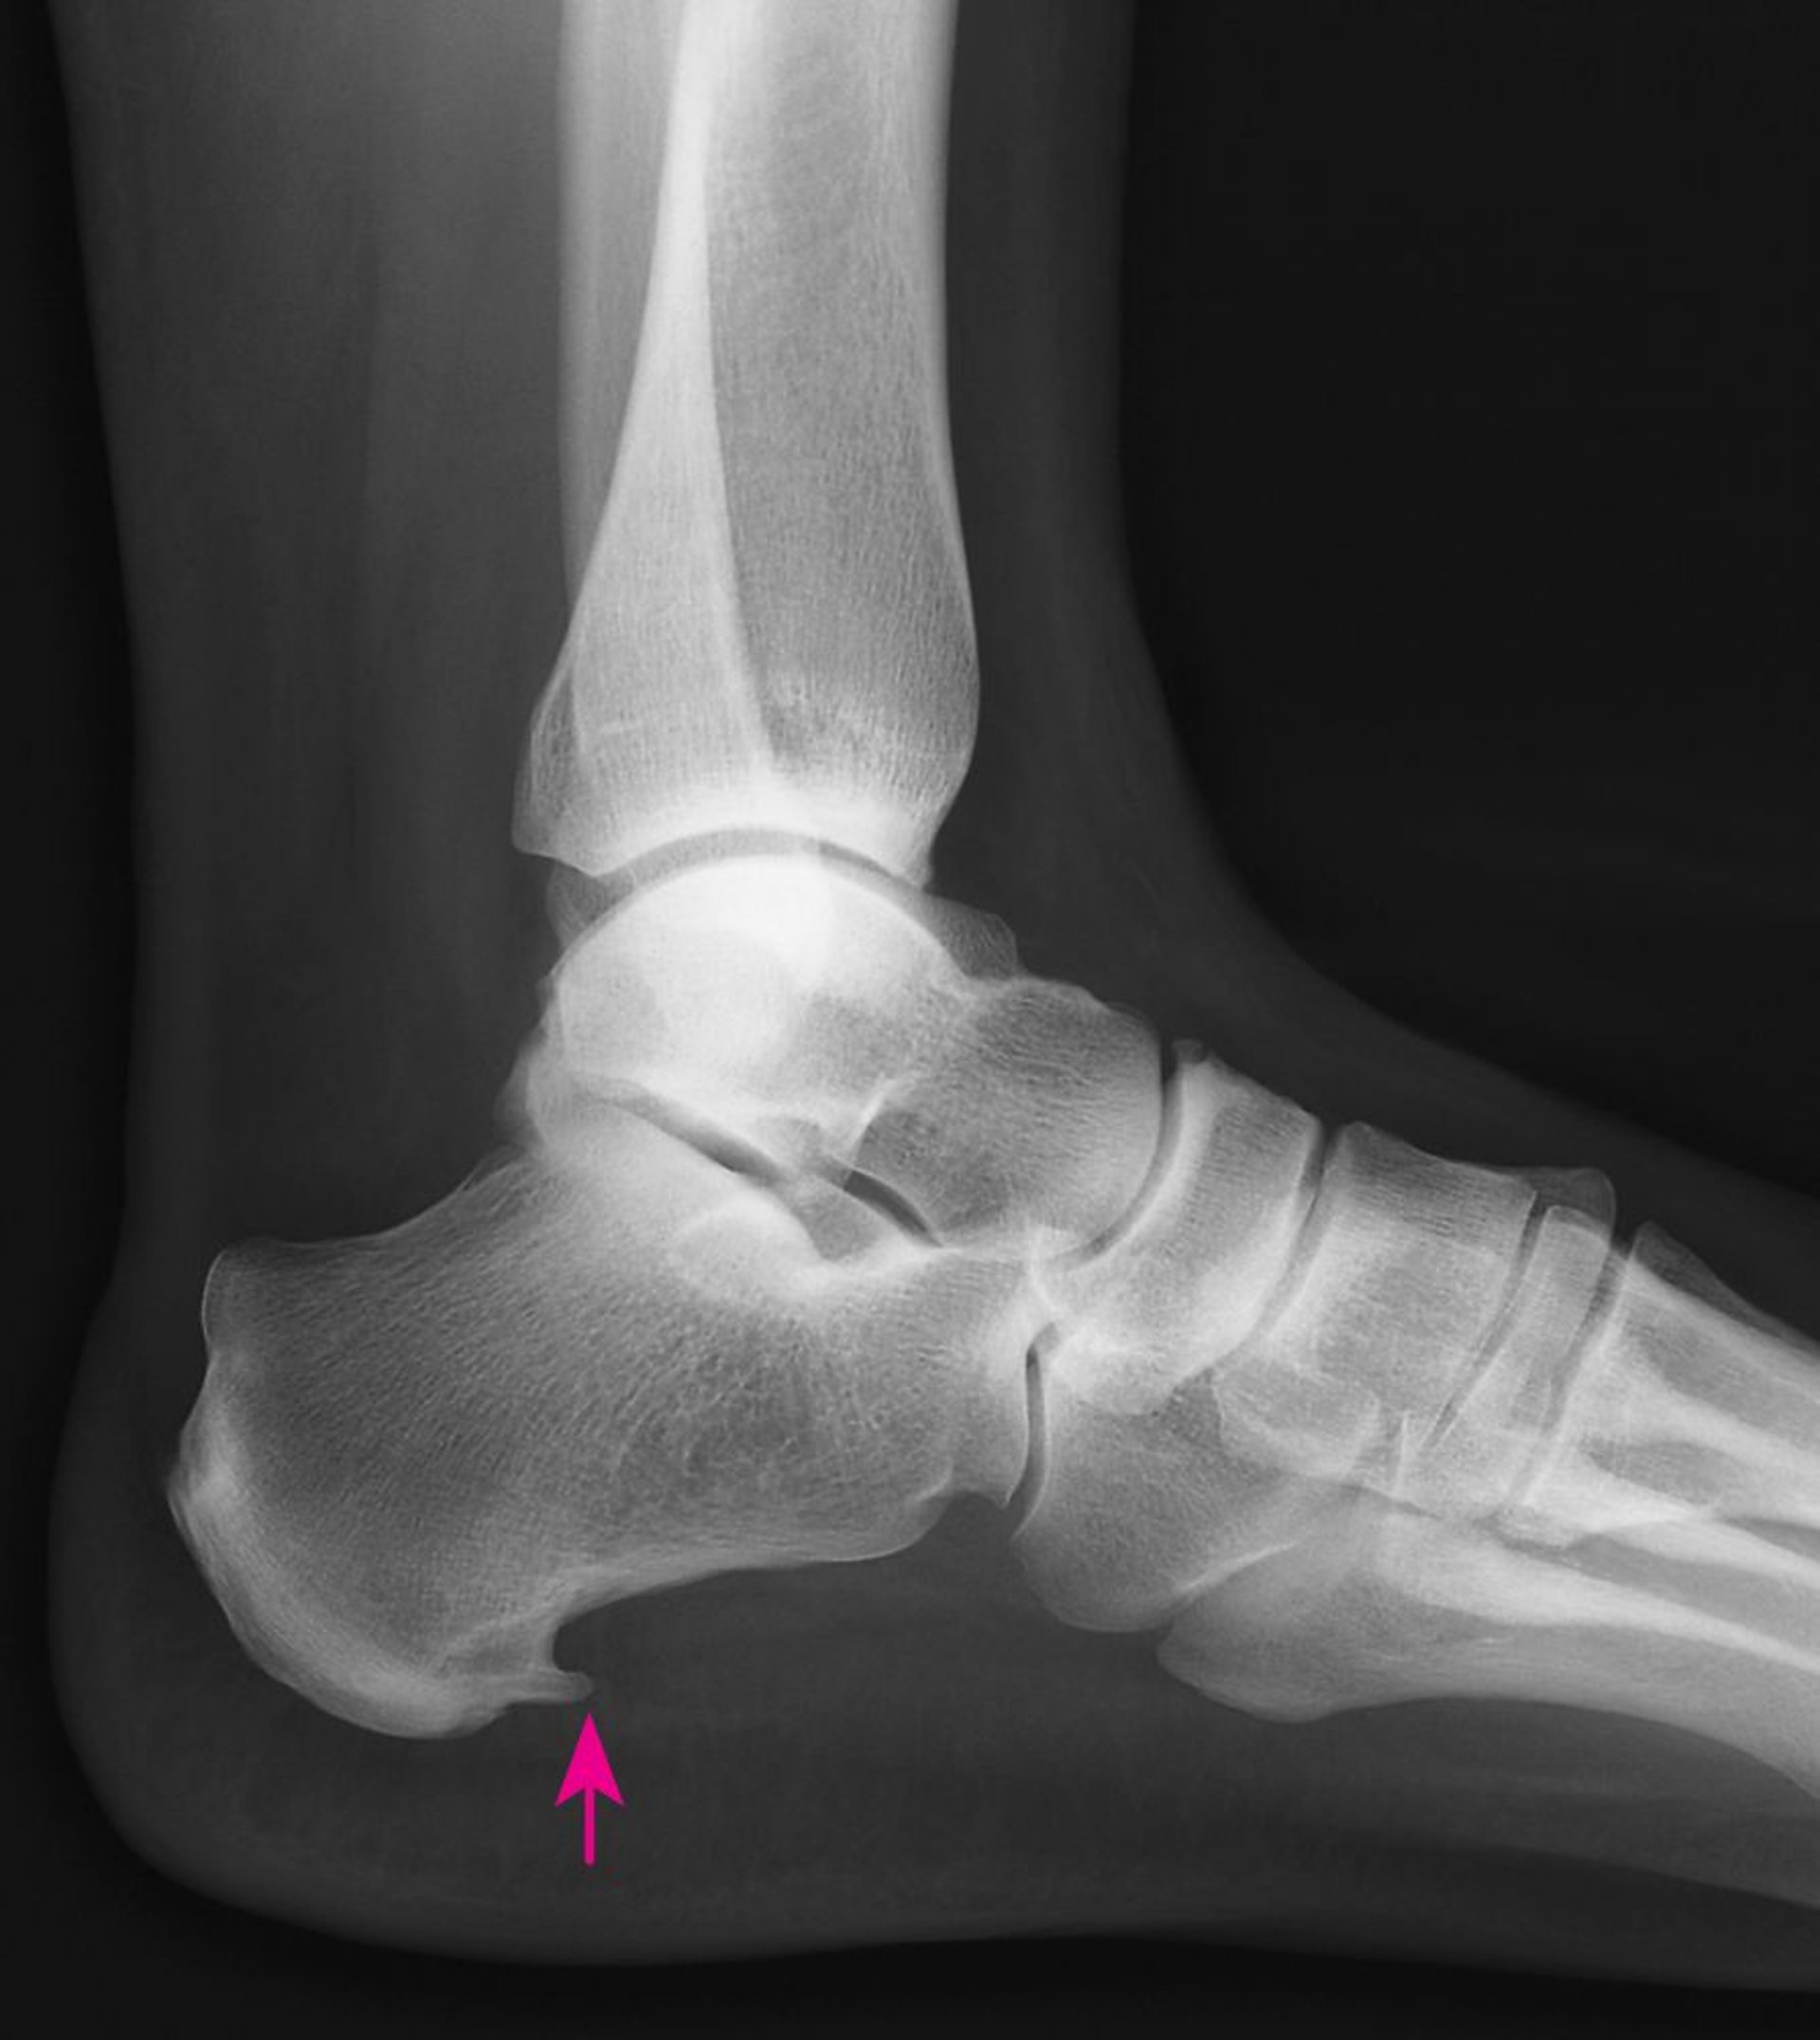

Épine calcanéenne

Cette radiographie montre une épine calcanéenne (excroissance osseuse pointue au niveau de l’os du talon [flèche]).

ZEPHYR/SCIENCE PHOTO LIBRARY